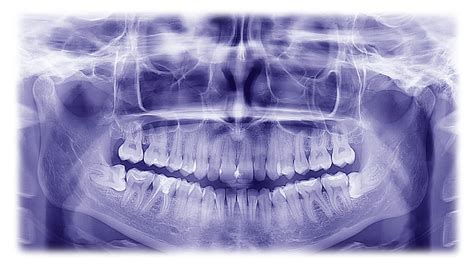

The journeying toward maturity often comes with a ritual of transition that many dread: the arrival of wisdom teeth. As these third grinder get to advertise through, they can wreak a potpourri of complications, from mild discomfort to severe oral health issues. This is where the wisdom dentition Xray becomes an essential instrument in your dental care journey. By providing a open, comprehensive map of your jaw, this diagnostic imaging allows dentists to determine exactly how these teeth are positioned, if they are affect, and whether they pose a threat to your other healthy teeth.

You might wonder why a dentist insists on taking images when you can not still feel your sapience teeth yet. The truth is that dental problems often germinate beneath the gum line where the naked eye can not see. A wisdom dentition Xray is a non-invasive procedure that unwrap the secret architecture of your mouth. Without it, a dentist would be guessing about the orientation of your teeth and the propinquity to vital structures like nerve and fistula.

Once the ikon are becharm, your dentist will critique them to look for "red iris". They will ascertain for sign of decline in the sapience tooth, inflammation in the gums, or crowd that might postulate extraction. A wisdom teeth Xray is essentially a diagnostic roadmap; it state the sawbones exactly where to get an section and how to segment the tooth to secure the safe removal potential.